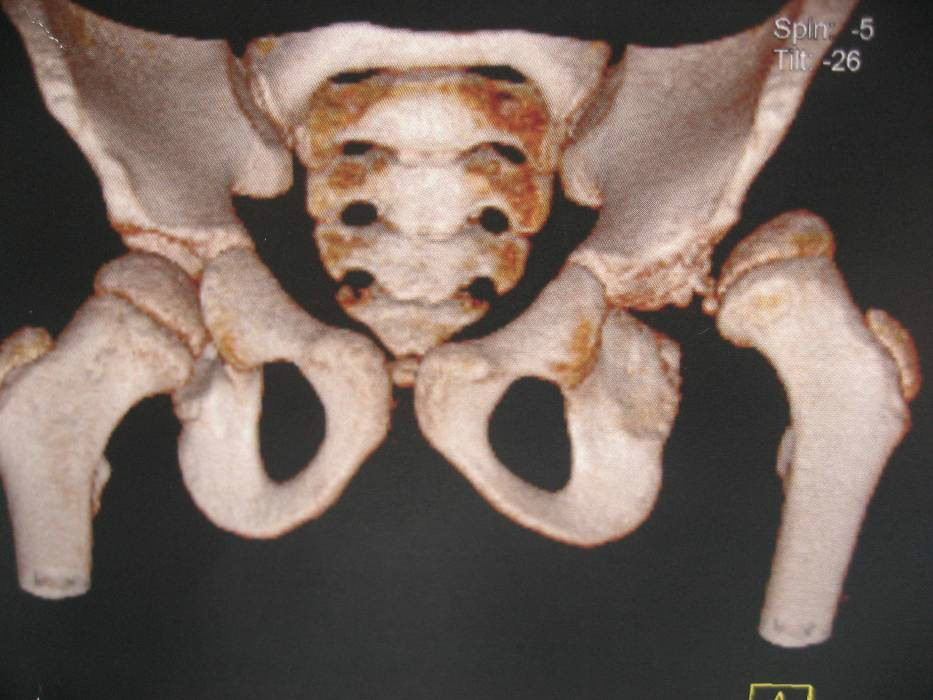

畸形骨盆

骨盆异常性难产

先天髋关节发育不良